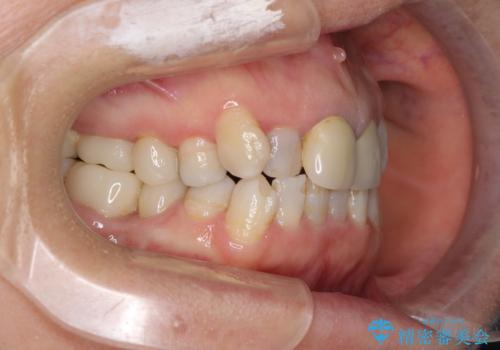

- 全顎的な歯列不正と、銀歯だらけの奥歯を気にして来院された患者様です。

奥歯の銀歯は、セラミッククラウンを装着するには歯の高さが不十分であり、そのままでは矯正治療を行うことが困難であるため、歯冠長延長術を行うこととしました。

また、根管治療の必要な歯がいくつかあるため、歯周外科治療の治癒期間を利用して根管治療を行い、その後インビザラインにて矯正治療を行うこととしました。

矯正治療後にはオールセラミッククラウンにて補綴治療を行うこととしました。